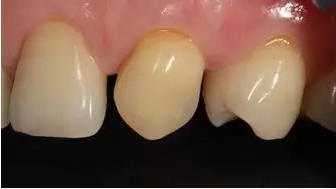

術后上前牙正面照

病例分享|復合樹脂微創(chuàng)美學修復關閉上前牙間隙

術后上前牙右側面照